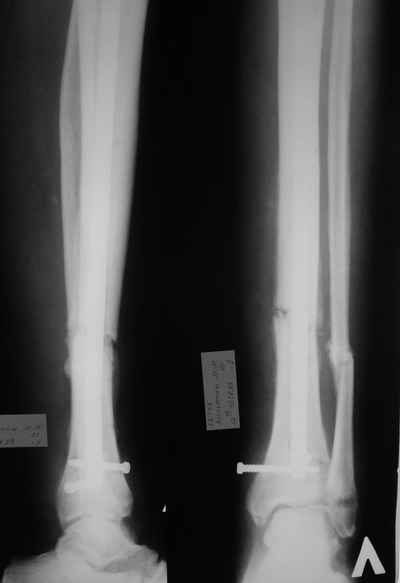

Итак - удалили стержень, воспалительный процесс к тому моменту купирован, наложили кастовую повязку и в течение 3 месяцев на контрольных рентгенограммах - признаки консолидации. Уже в сентябре, т.е черз 5 месяцев после нагноения пациент вернувшиь с подвождной охоты привез здорового сазана - основная жалоба - ноги побаливают после длительного лпаваня в ластах. Прилагаю снимки через год после удаления стержня. Вот такая, на этот раз счастливая казуистика.

Уважаемые коллеги, спасибо всем за участие. Сегодня просто просмативал старые страницы, да и пациента относительно недавно вспоминали. Случай подошел к логическому завершению: